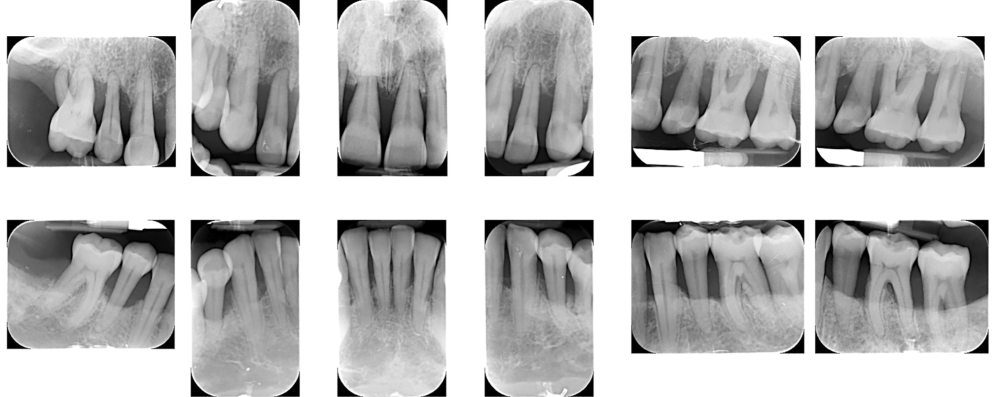

Avant toute intervention chirurgicale, un assainissement parodontal a été effectué. Les deux arcades ont été traitées afin de stabiliser l’environnement biologique (fig. 1). L’analyse complète du volume osseux et gingival a donc été réalisée à partir d’une situation clinique compatible avec une prise en charge implantaire ; un parodonte sain réduit (fig. 2).

L’empreinte optique, les photographies et le CBCT ont permis une fusion précise des données numériques pour planifier les axes et positions implantaires en fonction du projet prothétique final (fig. 3, 4).

Les implants ont été positionnés, sous guidage complet, dans le volume idéal anticipé avant les extractions, assurant un contrôle tridimensionnel précis (fig. 5). Cette approche a permis une procédure minimalement invasive et une préservation tissulaire optimale. Une prothèse immédiate imprimée a été adaptée aux contours gingivaux et au positionnement implantaire (fig. 6).